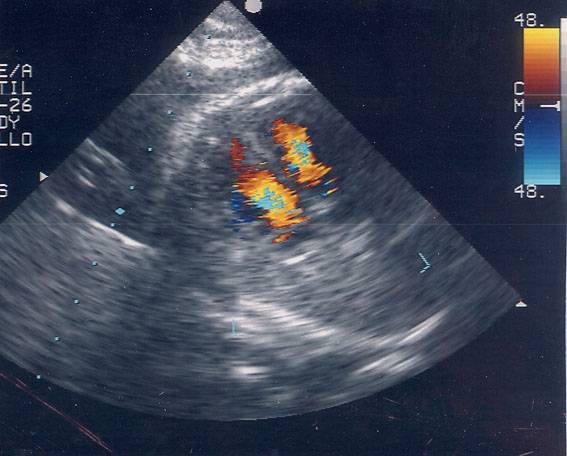

Ecocardiografía

Ecografía del corazón de un feto. Foto: Hospital La Paz de Madrid.